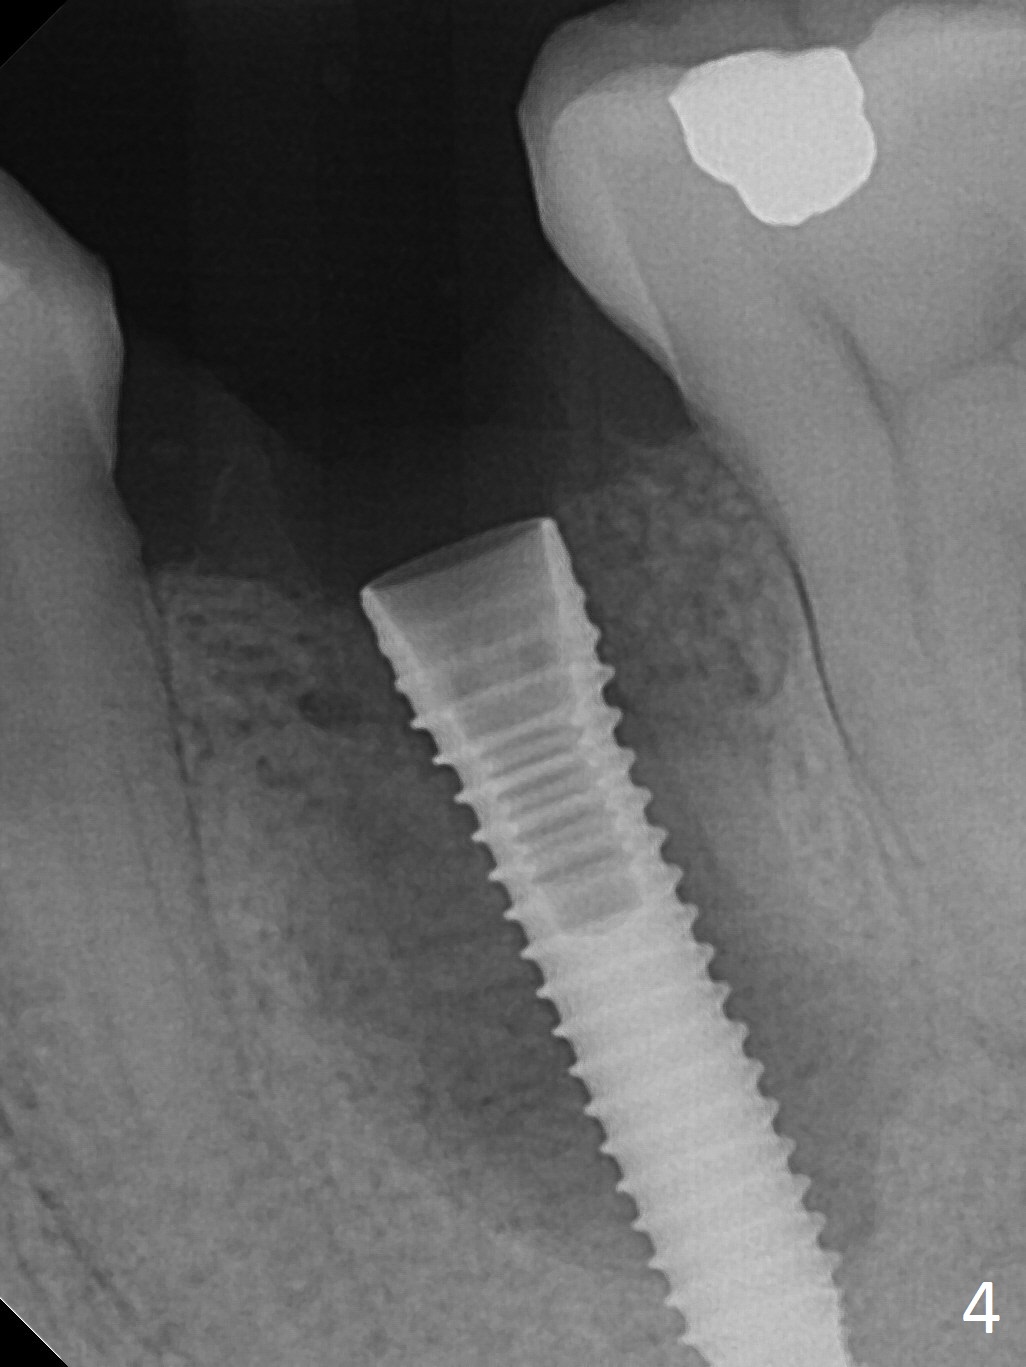

Extraction of the lower left 2nd premolar with vertical fracture (Fig.1,2 >) is easy because of peri-radicular radiolucency. The apical end of the osteotomy is not shown with a 2 mm pilot drill (Fig.3) or a 3.8x18 mm implant (Fig.4) in place. It appears that the implant is not placed deep enough. Following 3-4 more turns of the implant and placement of a 5.5x4(3) mm abutment (Fig.5 A), allograft is placed (*). A postop panoramic X-ray is taken (Fig.6); the osteotomy could have been deepened to reduce the possibility of periimplantitis. Retrospectively, the panoramic X-ray should be taken after use of the pilot drill. The bone around the implant appears to have regenerated 4 months postop (Fig.7,8). Bone density appears to continue increasing 9 months postop (i.e., 4.5 months post cementation, Fig.9). Bone loss is minimal 2 years post cementation (Fig.10).